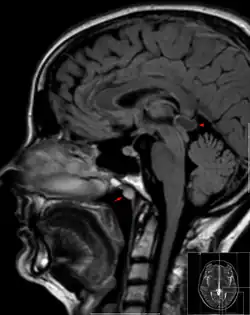

| Tornwaldt cyst imaged on sagittal MRI (FLAIR). The cyst appears hyperintense in the midline of the nasopharynx (arrow). In this case there is also a cyst of the pinealis gland (arrowhead) showing a signal intensity slightly higher than the CSF. | |

A Tornwaldt cyst (also spelt as Thornwaldt or Thornwald[1]) is a benign cyst located in the upper posterior nasopharynx. It was first described by Gustav Ludwig Tornwaldt. It can be seen on computed tomography (CT) or magnetic resonance imaging (MRI) of the head as a well-circumscribed round mass lying in the midline. In most cases, treatment is not necessary. Indications for treatment include symptomatic lesions, large lesions (>1 cm), or lesions adjacent to the eustachian tube orifice.[2]